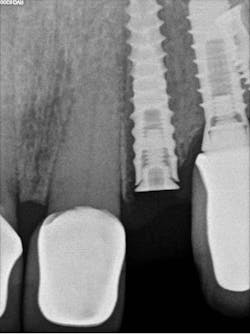

Maintaining initial stability is important when an implant is placed in a compromised extraction site, since there is less bone-to-implant contact there than in a healed site. Because of its architecture, the Ditron Ultimate implant offers a very high initial stability and strong abutment connection. The implant profile uniformly distributes the stress directly to the bone, which results in a more even distribution of force and lower long-term crestal resorption. This implant system has a good aggressive thread profile and a secure abutment connection, which are both key characteristics. The microthreads on the implant’s reverse conical neck (RCN) greatly increase the implant’s ability to resist axial displacement, and the mechanical stimulus the microthreads provide helps to preserve the peri-implant marginal bone. By inserting an Ultimate implant, 5.57 mm3 of bone will be saved compared to that of a non-RCN implant.7

Second visit: After two months of healing, final impressions were taken.

The implant was allowed to heal for two months before impressions were taken. The final zirconia crown was delivered two weeks later (figure 6).